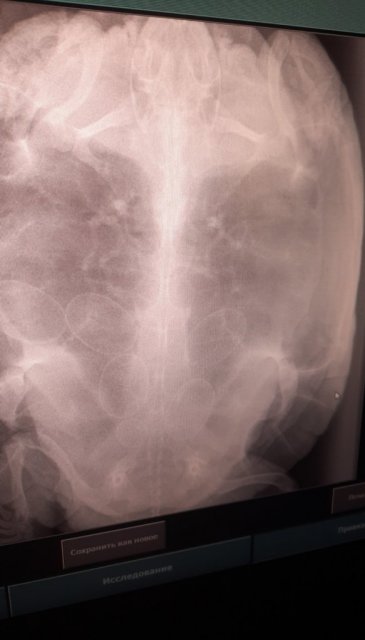

Татьяна.04 Ваше имя: Татьяна Локация: Россия, Люберцы Опубликовано: 16 июня 2024 Опубликовано: 16 июня 2024 Снесла только одно яйцо? Их может быть больше. Наша, одна из трёх, периодически сносит яйца. Мы всегда делаем рентген, сразу, как только она начинает беспокойно себя вести. Рентген можно в любой вет.клинике сделать, на снимке будет понятно сколько там яиц вообще и в каком они положении. Должны выйти все

Татьяна.04 Ваше имя: Татьяна Локация: Россия, Люберцы Опубликовано: 28 июня 2024 Опубликовано: 28 июня 2024 А наша никак до конца снестись не может. Рентген показал 6 яиц ещё в апреле. Начала нестись по одному с перерывами в несколько дней и недель. Ещё два осталось. Удивительный факт, что сразу после того, как снеслась 28.03 (вышли все 6 яиц) , через неделю начала проявлять беспокойство, отказ от еды и т.п. Мы сразу к герпетологу, сделали рентген и обнаружили вновь 6 яиц! Врач только развёл руками, говорит, что первый раз с таким сталкивается. Очень короткий период для их формирования

Татьяна.04 Ваше имя: Татьяна Локация: Россия, Люберцы Опубликовано: 28 июня 2024 Опубликовано: 28 июня 2024 Дело в том, что 28.03 она снесла все 6. А в начале апреля как-то сформировались ещё новые 6,( за неделю), одно было недоразвитое, на снимке оно самое маленькое, внизу. Вот что удивительно. Вот, потихоньку, с большими перерывами снесла в июне 4, ещё остались два. Так-то да, несутся они 2 раза в год, с хорошим перерывом между кладками. А у нас интервал был - неделя (!) Интересно, у других черепах такое бывало?